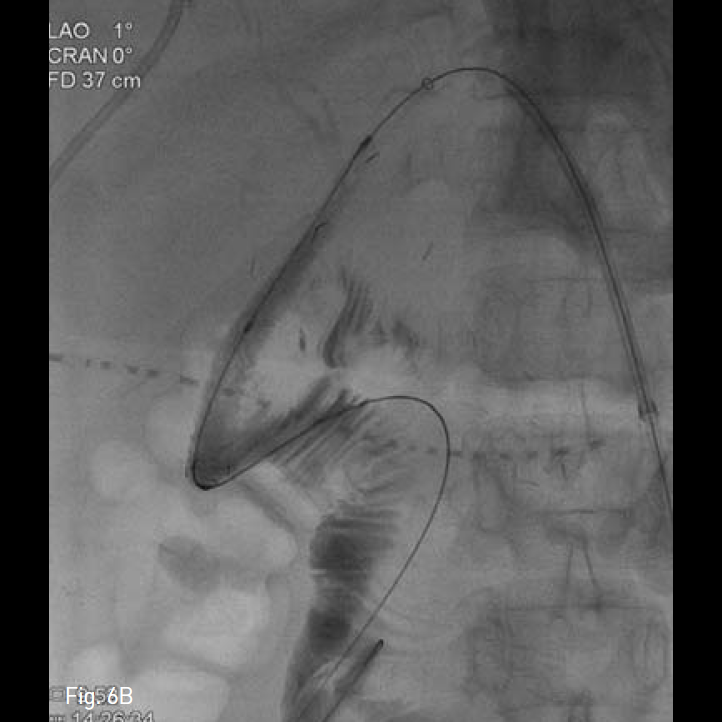

Fig. 6

Anti-reflux stent consist of inner covered stent and outer uncovered stent A. Finally, we performed biliary stenting to efferent bowel loop across choledocho-duodenostomy site B.

시술방법 및 재료

이전 시행된 좌측 경피경간 담도 배액관을 동해 담관 조영술을 시행하여 총담관 - 십이지장 분합부를 확인하고, 0.035-inch guide wire(Terumo, Tokyo, Japan)와 5-Fr KMP catheter(Cook, Bloomington, IN, USA)를 이용하여, wire를 원위부 십이지장에 거치 후, 분합부를 가로질러 직경 10mm, 길이 8cm의 Anti-reflux designed, GD type biliary stent(TaeWoong Medical, Gimpo, Korea)를 설치하였다(Fig. 6B). 시술 후 담관조영술을 통해 스텐트의 개방성과 적절한 위치를 확인 한 후, 추적 관찰을 위해 다시 8.5-Fr pigtail형drainage catheter(Cook, Bloomington, IN, USA)을 거치하였다.